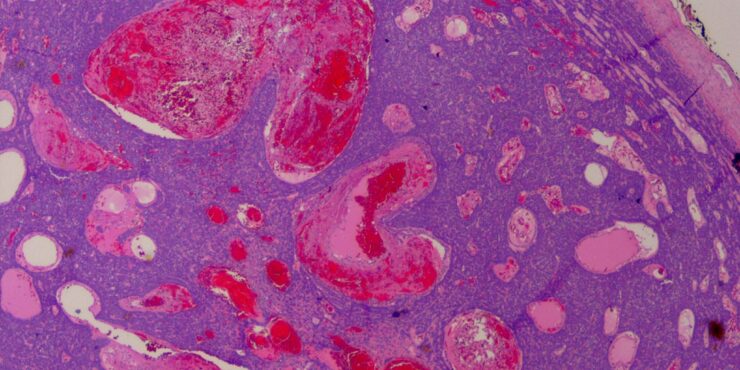

Read MoreSpindle cell hemangioma = وعاؤوم مغزلي الخلايا